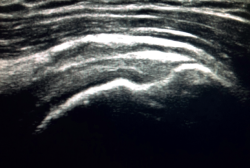

The characteristic ultrasound image of tendinosis consists of local or diffuse thickening accompanied by a hypoechogenic and heterogeneous appearance of the tendon (Figure 3). A fine hypoechoic line over 2 mm in thickness between the tendon of the supraspinatus and the subdeltoid adipose tissue corresponds to subacromial-subdeltoid bursitis, and the presence of fluid in the bursa is related to a high probability of partial or complete injury of the tendon of the supraspinatus muscle(26). In order to achieve greater diagnostic accuracy and distinguish between an inflammatory process and a normal small amount of fluid in the bursa, we should take into account that bursitis, tenosynovitis and tendinitis are characterized by the presence of hyperechoic zones with areas of enhanced flow in the Doppler ultrasound study. Both bursal and articular partial ruptures appear as a hypoechoic discontinuity in the tendon that does not vary on modifying the inclination of the ultrasound probe in either the long axis of the tendon nor its short axis(19). This latter aspect is important in order not to confuse partial lesions with anisotropic phenomena, which are a change in tissue behaviour according to the ultrasound angle of incidence(27)(Figure 4).

Figure 4. Anisotropy at the insertion of the tendon of the supraspinatus muscle. Not to be confused with partial thickness injury.